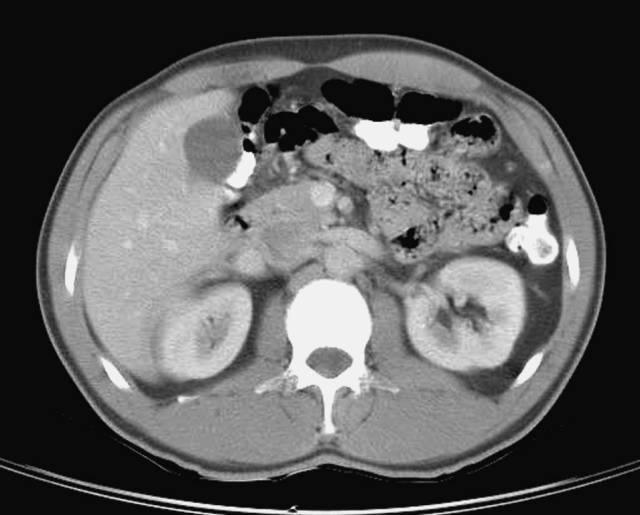

第三层

1、肝右叶;2、肝尾状叶;3、下腔静脉;4、肝门静脉;5、腹直肌;6、肝圆韧带;7、肝左叶;8、十二指肠降段;9、腹白线;10、肠系膜上动脉;11、腹腔干;12、胃;13、脾静脉;14、胰腺;15;空肠;16、横结肠;17、降结肠;18、左结肠静脉;19、腹外斜肌;20、膈肌;21、奇静脉;22、髂肋肌(胸段);23、胸导管;24、胸椎;25、棘肌;26、椎管和脊髓;27、腹主动脉;28、半奇静脉;29、最长肌;30、肾上腺动脉;31、左侧肾上腺;32、左肾;33、左肺;34、背阔肌;35、脾脏;36、肝门区;37、圆韧带凹痕;38、肝十二指肠韧带;39、网膜孔;40、网膜囊/大网膜;41、胰淋巴结;42、右膈下隐窝;43、肝淋巴结;44、腰淋巴结;45、膈上淋巴结;46、后纵隔;47、脾门;48、左结肠旁沟。